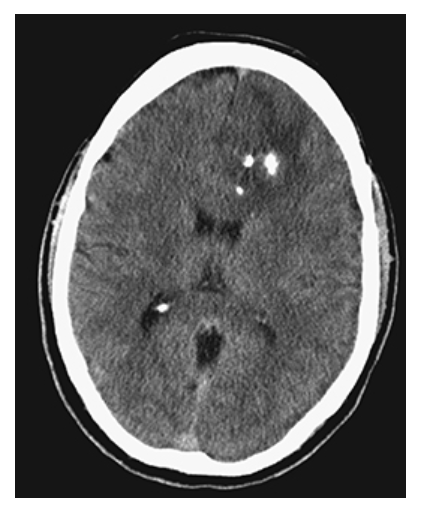

What is A

Tuberous Sclerosis. PD axial and postcontrast T1W

What is B

Tuberous Sclerosis. PD axial contrast shows an enhancing left subependymal giant cell astrocytoma in the foramen of Monroe and an enhancing subependymal nodule in the trigone of the left lateral ventricle.